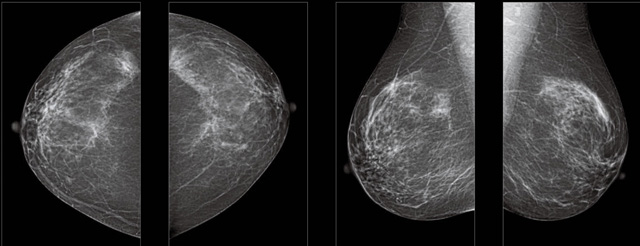

首先不同年齡階段的乳腺篩查頻次種類不一樣。青春期女性第二性征明顯發(fā)育開始,每個月進行自我乳腺檢查。20-30歲的女性就不推薦進行乳腺檢查,因為年輕女性的乳腺組織非常緊急。鉬靶X光線等檢查的射線不能辨別腫塊跟腺體。身體就白吸收了輻射,影響了身體健康。每個月自檢一次就是在洗澡時候,對著鏡子看看乳房外觀正常,皮膚潰爛、腫塊、顏色改變、再摸一下有沒小疙瘩。乳腺高危人群,特別是有乳腺CA遺傳傾向的女性,乳腺導管跟小葉不典型增生,原位癌。30歲前有乳房放療的女性。乳腺癌篩查可以把年齡提前到40歲前。40到70歲的女性可以在適合的機會篩查。

采用影像檢查技術(shù)來發(fā)現(xiàn)疑似特定病檢查跟人群的普查。一到兩年進行一次X光線的乳腺檢查。記過是C或者D型,可以加上B超協(xié)同。還可以一年一次核磁共振MRI檢查。70歲以上的女性認為絕經(jīng)的女性是比較安全的。實際上也有乳腺癌的風險。65歲以上風險也很大。也是需要進行機會性篩查。